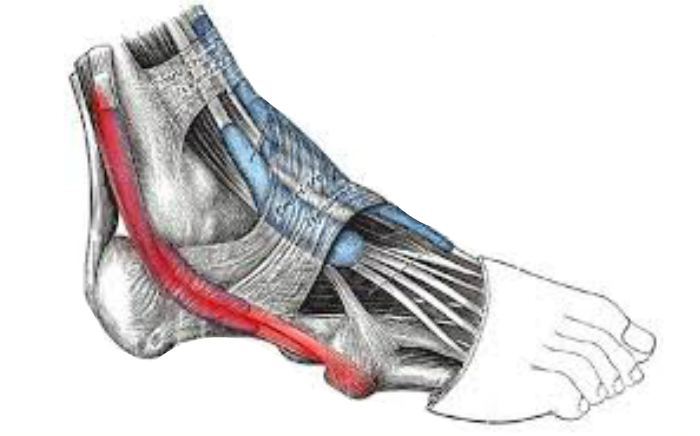

Common Foot & Ankle Disorders

Did you know the foot has 26 bones, 33 joints, 107 ligaments, 19 muscles, and numerous tendons? These parts all work together to allow the foot to move in a variety of ways while balancing your weight and propelling you forward or backward on even or uneven surfaces. It is no wonder that 75 percent of all Americans will experience foot problems at one point or another in their lifetimes.